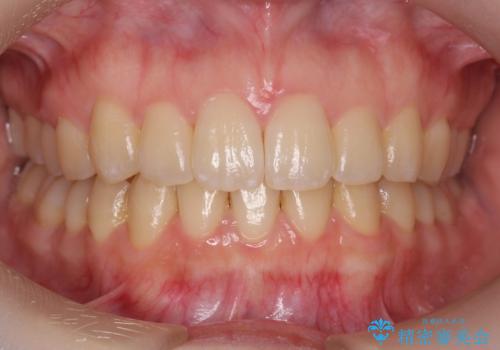

奥歯のかみ合わせも妥協しない インビザライン治療

- 歯のがたつきを主訴に来院。

左右とも奥歯のがたつきがあり、左奥はすれ違っていました。

また、右奥は反対咬合になっていました。

患者様が気づかない範囲で妥協して終わるということをせず、しっかり奥歯に部分矯正を用いて大きな問題を解決してからインビザライン治療に入りました。

下の前歯を一本抜歯しています。(抜歯の本数は最小限にしています。)